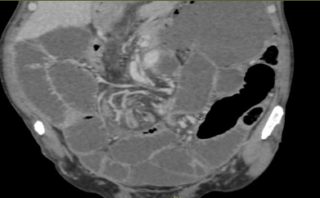

Figure 3 : Coupe frontale du scanner montrant le signe du tourbillon (whirl sign).

Scanner abdominal (TDM) :

Le scanner a révélé une distension de l’intestin grêle située en amont de deux « signes du bec » (beak signs) contigus. Ce tableau clinique est compliqué par un volvulus du cæcum par torsion, avec la présence caractéristique d’une image en tourbillon (whorl sign), sans que des signes de complications majeures ne soient visibles à ce stade.